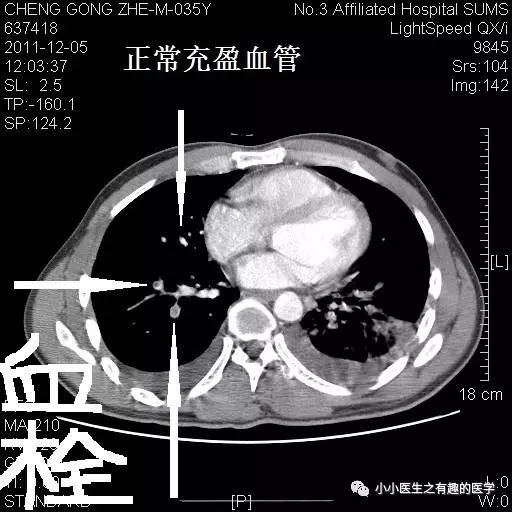

看看下图,这才是正常的肺动脉。

再复习一下,肺动脉乃人字形。

再来一例。我读研究生期间的病人。

小小的充盈缺损。

看小小血栓,也不难。